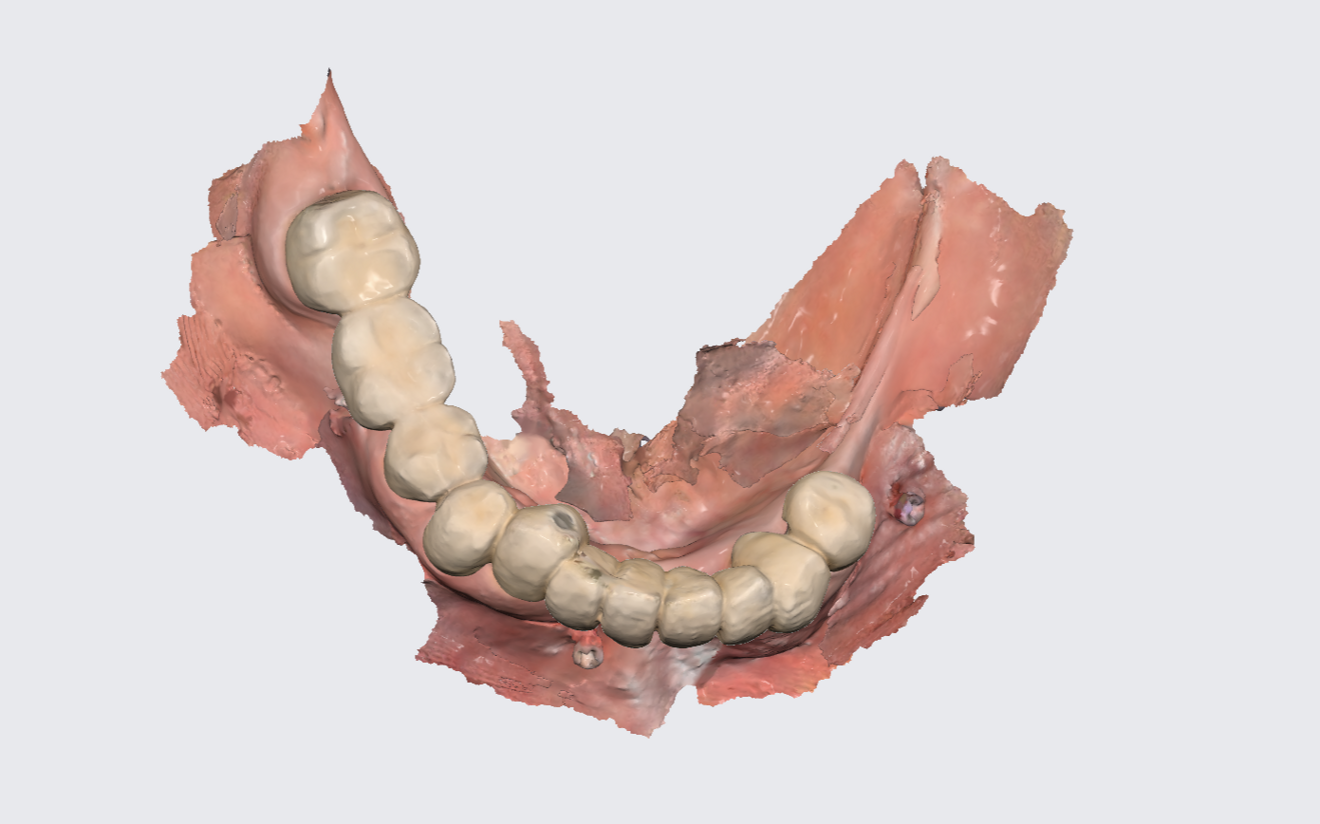

Figs. 2a & b: Intra-oral scans of the pre-op situation.

Fig. 2b

Intra-oral examination revealed compromised mandibular dentition, an old fixed prothesis, missing posterior teeth on the left side, periodontal involvement and gingival inflammation. A panoramic radiograph was obtained, and the findings were reported to the patient (Figs. 1a & b; 2a & b). Both mandibular canines had visible periapical radiolucencies. A CBCT scan was performed for a more detailed assessment of the alveolar bone anatomy (Figs. 3a & b). Temporomandibular joint examination revealed no indication of dysfunction (crepitus, clicking or pain).